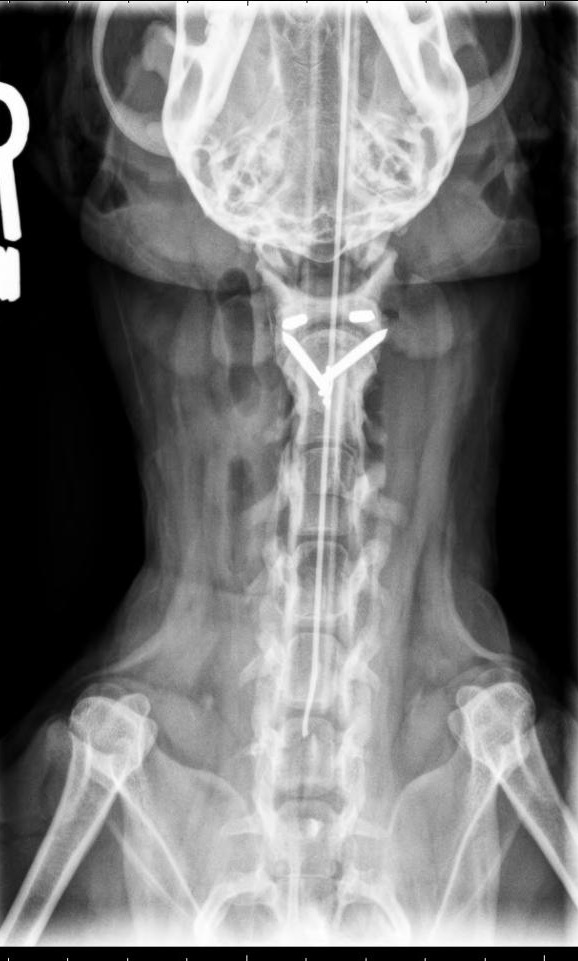

A. Atlantoaxial subluxation. The post-operative radiographs are shown below. Note the absence of the dens.